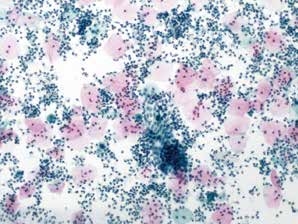

图7-8 满意样本(低倍、液基、巴氏染色)

鳞状上皮细胞的数量约为5 000个,背景中大量的炎细胞。满意样本的临界状态。